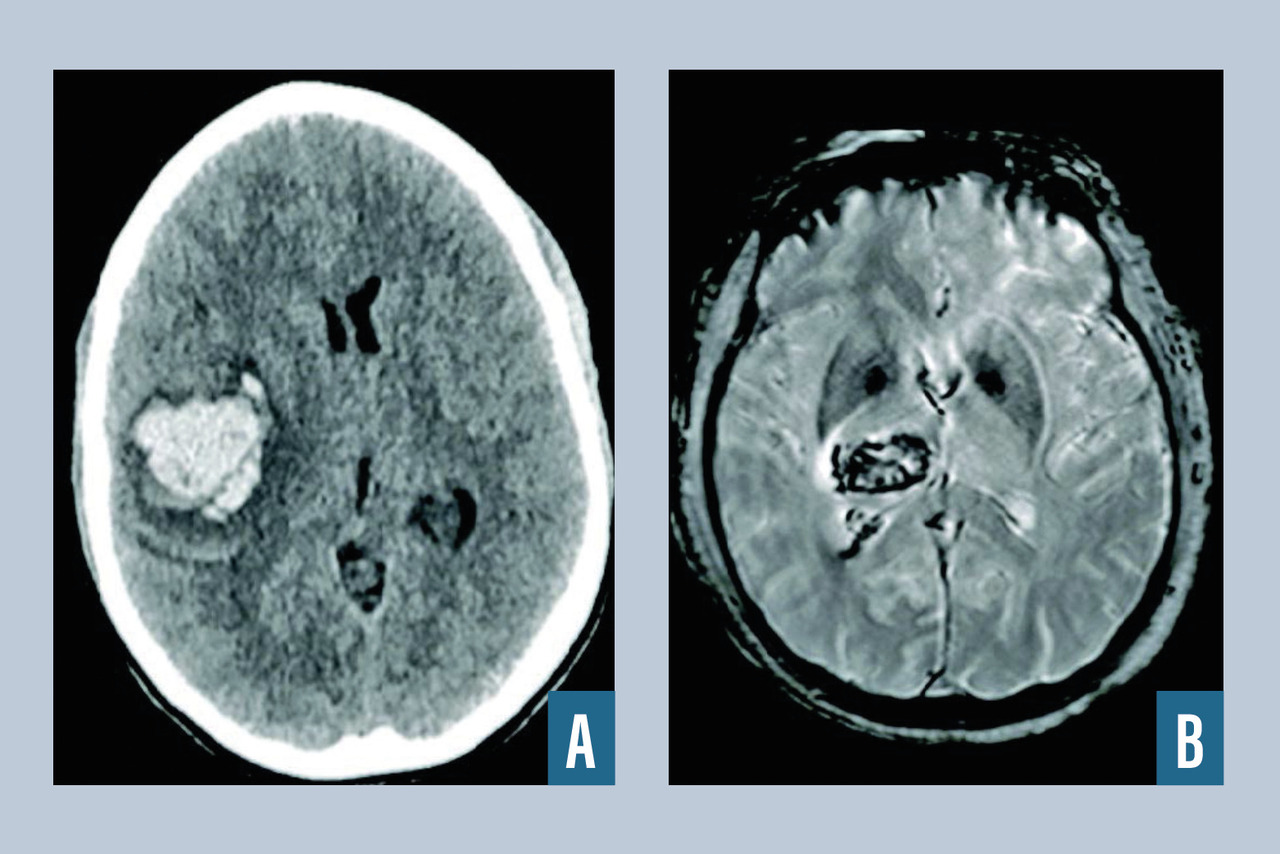

L’hématome intracérébral est une collection de sang consécutive à la rupture d’un vaisseau intracrânien (fig. 2 ). L’hypertension artérielle est la première cause, et l’hémorragie est alors très souvent localisée au niveau des noyaux gris centraux. Lorsque l’hémorragie est située en superficie, elle est dite lobaire, et après 50 ans, le diagnostic d’angiopathie amyloïde est fréquemment rencontré après exclusion des autres diagnostics (tumeurs, traumatisme…). Une autre cause est la rupture d’une malformation vasculaire, que ce soit une malformation artérioveineuse, un anévrisme ou un cavernome. Parmi les autres causes, on cite la thrombophlébite cérébrale et les troubles de la coagulation spontanés ou iatrogènes (traitements antithrombotiques). Le scanner cérébral, qui est l’examen de référence en cas d’hémorragie cérébrale, met en évidence une plage en hyperdensité et est le plus souvent complété par un scanner cérébral avec injection et un angioscanner cérébral à visée étiologique (recherche de tumeur, de malformation vasculaire, de thrombose veineuse cérébrale). L’IRM cérébrale avec ARM peut être intéressante lorsque le scanner n’est pas contributif pour rechercher une cause de l’hémorragie (stigmates de maladies des petites artères liées à l'âge et à l'hypertension artérielle, angiopathie amyloïde, tumeur cérébrale). En l’absence de cause retrouvée à la phase aiguë, l’IRM cérébrale injectée doit être réitérée à trois mois pour s’assurer de l’absence de lésion sous-jacente. Le recours à l’artériographie cérébrale est fréquent dans le cadre du bilan étiologique de l’hématome du sujet jeune, en l’absence de cause évidente.